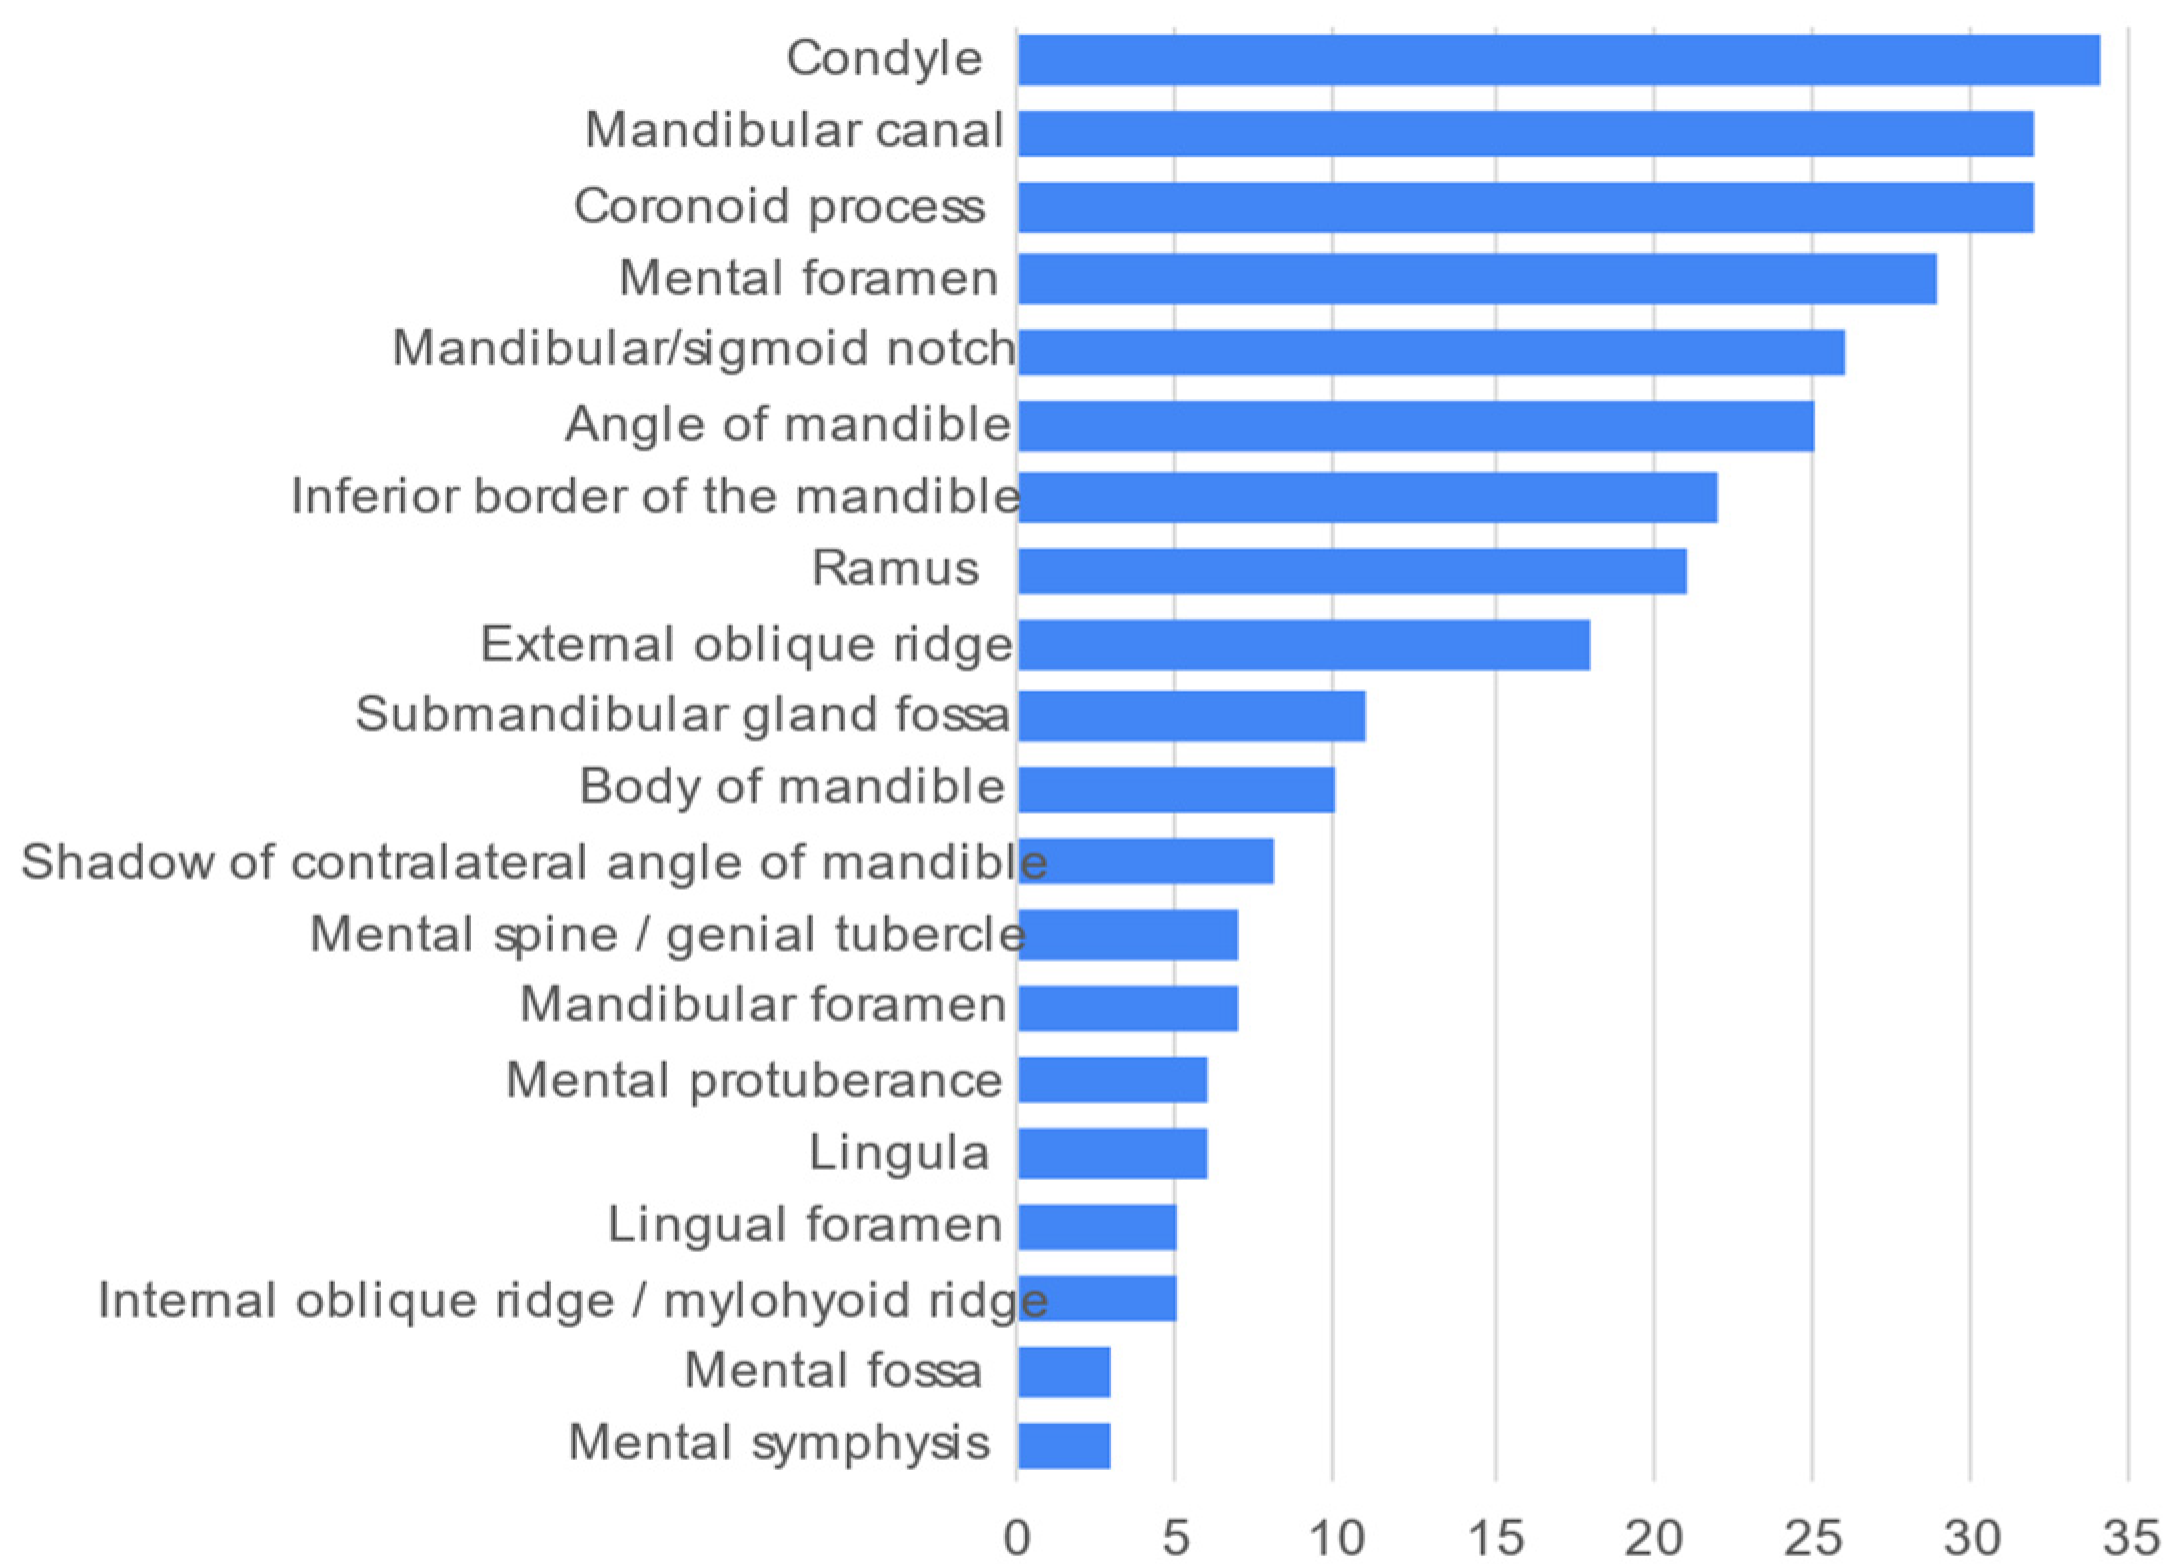

3. Results

| Mandibular landmarks | ||

| Mandibular landmarks | ||

| Mandibular | 8.2 ± 4.0 | 0; 16 |